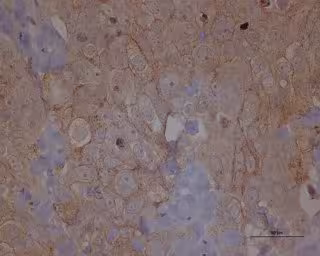

Metástasis cáncer de ovario

Metástasis cáncer de ovario - IDIBELL-ICO - Archivo